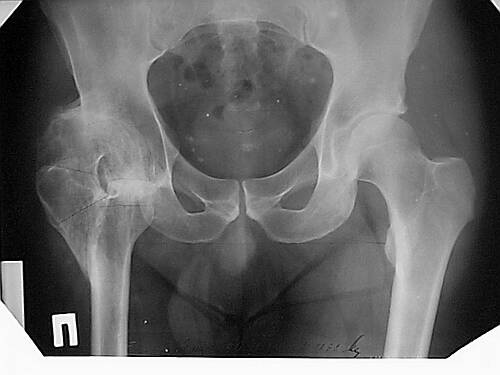

Наше общее мнение - проведение клиновидной остеотомии в зоне дополнительной точки опоры с ее иссечение и укорочением бедра, протезирование ножкой Вагнера.

Похожий случай представляем на ретгенограммах. Операция выполнена в 1996 г.